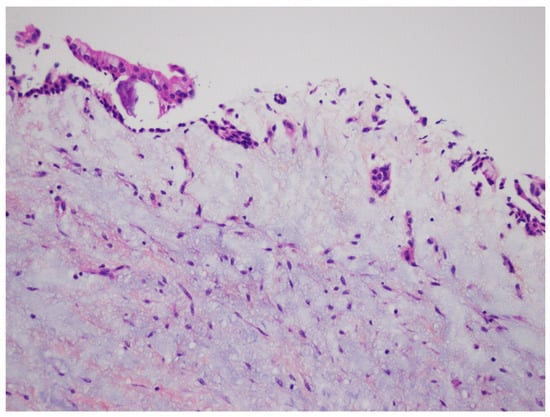

Figure 3.

Histopathological examination of the enucleated specimen from case #1 showing an uninflamed fibrous cyst wall lined by a thin cuboidal epithelial lining (H&E, ×40).

DC is the second most common odontogenic cyst occurring in association with an unerupted tooth. It develops from the accumulation of fluid between the reduced enamel epithelium of the dental follicle and the crown of an unerupted tooth (Figure 14). The microscopic features of DC are dependent whether it is not inflamed or inflamed [,,,]. In the case of non-inflamed DC, the epithelial lining is formed by two to four layers of cuboidal/squamous non-keratinizing cells without rete ridges and a flat epithelium-connective tissue interface (Figure 3). The cyst wall consists of fibrous or fibro-myxoid tissue containing considerable glycosaminoglycan ground substance. Small islands or cords of inactive-appearing odontogenic epithelial rests are usually present within the connective tissue.